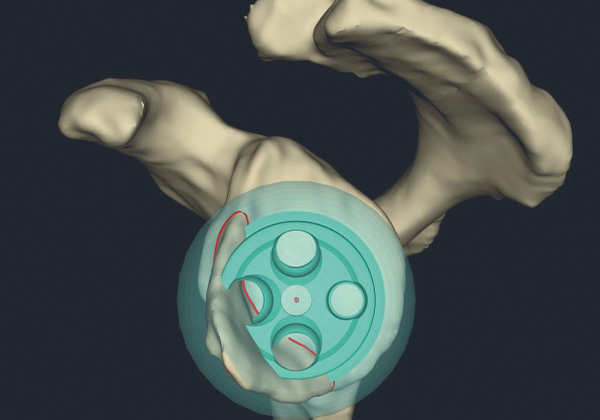

Bei diesem künstlichen Gelenk wird das Prinzip des Gelenkes „umgedreht“ - invertiert. Aus der Kugel (Oberarmkopf) wird eine Pfanne (Schulter) und aus der Pfanne wird eine Kugel. Dadurch entsteht gegenüber dem anatomischen Prinzip eine innere Führung des Gelenkes, die nicht auf die volle Funktionsfähigkeit aller vier Sehnen der sogenannten Rotatorenmanschette, die den Oberarmkopf in der Schultergelenkpfanne stabilisiert, angewiesen ist. Dieses Prinzip führt gegenüber dem anatomischen Gelenk verlässlicher zu guten Ergebnissen und es kann zudem ein weitaus breiteres Spektrum von Erkrankungen des Schultergelenks behandelt werden.

Inverse Schulterprothesen kommen bei Verschleißerkrankungen des Gelenkes, im Endstadium der Rotatorenmanschettenerkrankung (Defektarthropathie) wie auch in der Behandlung von Oberarmkopfbrüchen und in der Revisionschirurgie zum Einsatz. Ein besseres Verständnis für die Gelenkmechanik des Inversen Gelenkes führte zu Weiterentwicklungen. Neue Implantatsysteme sind durch eine höhere Modularität mit diversen Anpassungsmöglichkeiten an die anatomischen und verschleißbedingten patienteneigenen Gegebenheiten gekennzeichnet. Durch den Einsatz von digitalen dreidimensionalen Planungen, die aus präoperativen CT – Untersuchungen der Patient*innen angelegt werden, ist es möglich, diese größere Modularität auf den jeweiligen Fall individuell anzuwenden.

Besonderes Augenmerk liegt dabei auf der Schulterblattseite – der Pfanne – des Gelenkes. Im Rahmen der Verschleißerkrankungen kommt es teils zu erheblichen Gelenkflächenabnutzungen. Durch die präoperativen dreidimensionalen Analysen ist es möglich, eine optimierte Positionierung des pfannenseitigen Implantates mit Ausgleich der Defektsituation - sei es durch körpereignen Knochen oder metallische Augmente - zu erzielen.

3D-Planung und gedruckte individuelle Instrumente

Fallweise kann zur besseren Umsetzung aus der Planung heraus patientenindividuell ein Instrumentarium mit Hilfe eines 3D-Druckers hergestellt werden. Dies führt zu achsengerechten Komponentenpositionen mit einer guten Beweglichkeit. Durch die optimale Zentrierung und Verringerung von Gelenkkonflikten ist zudem eine deutliche Verbesserung der Dauerhaftigkeit der künstlichen Gelenke zu erwarten.